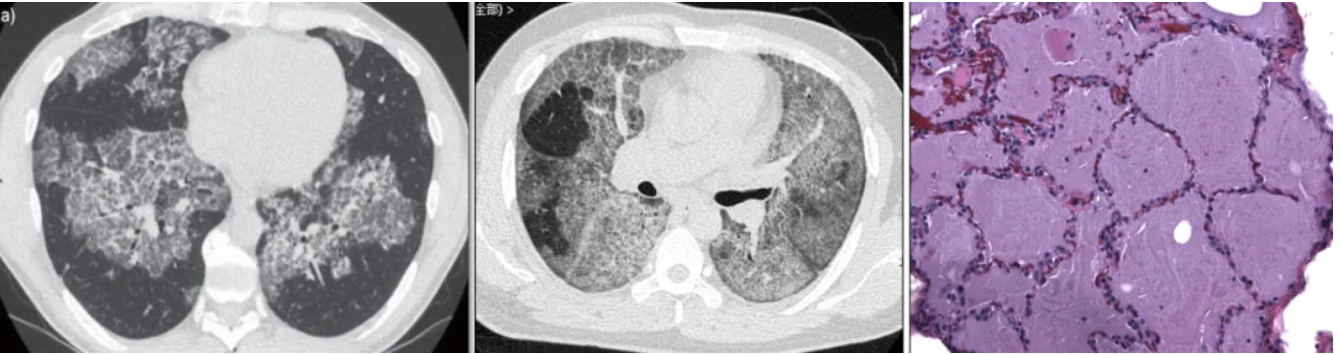

“活动”判断:一方面可观察是否出现持续或进展性的症状,如呼吸困难、咳嗽、咳痰、体重减轻等;还有功能评估,包括肺功能明显异常(FVC或DLCO)、动脉血气分析可能提示低氧血症,以及比较直观的胸部影像学检查——HRCT可见新发或较前加重的PAP特征性浸润影,同时还需排除肺内病灶是否为其他病因或并发症所致。

对于疑诊PAP的患者,指南推荐BAL作为诊断评估中的重要环节。(强推荐,极低级别证据),因为灌洗液相对“有特色”:乳白色、静置沉淀,无定形嗜酸性物质、泡沫状巨噬细胞,淋巴细胞升高。

BALF检测内容包括细胞计数分类、PAS染色和微生物学检测;推荐原因:侵入程度低,低风险,诊断价值高。